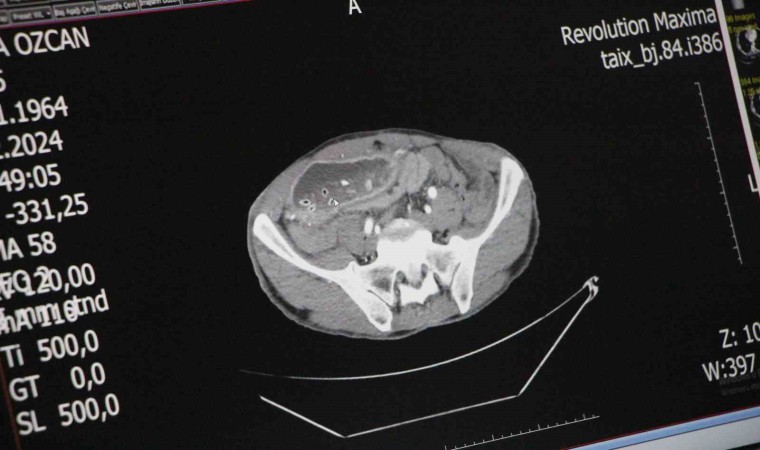

Yapılan endoskopi ve tomografi çekiminin ardından gerçekleşen ameliyatında çıkış kısmı daralan midesinin 10 kattan fazla büyüyerek karın boşluğunu sardığı görüldü. Mide ve karaciğer arasında oluşan doku bandının mideyi ikiye ayırdığını gören Genel Cerrah Doç. Dr. Yavuz Pirhan, ince barsak ile mide arasına yeni bir kanal yaptı.